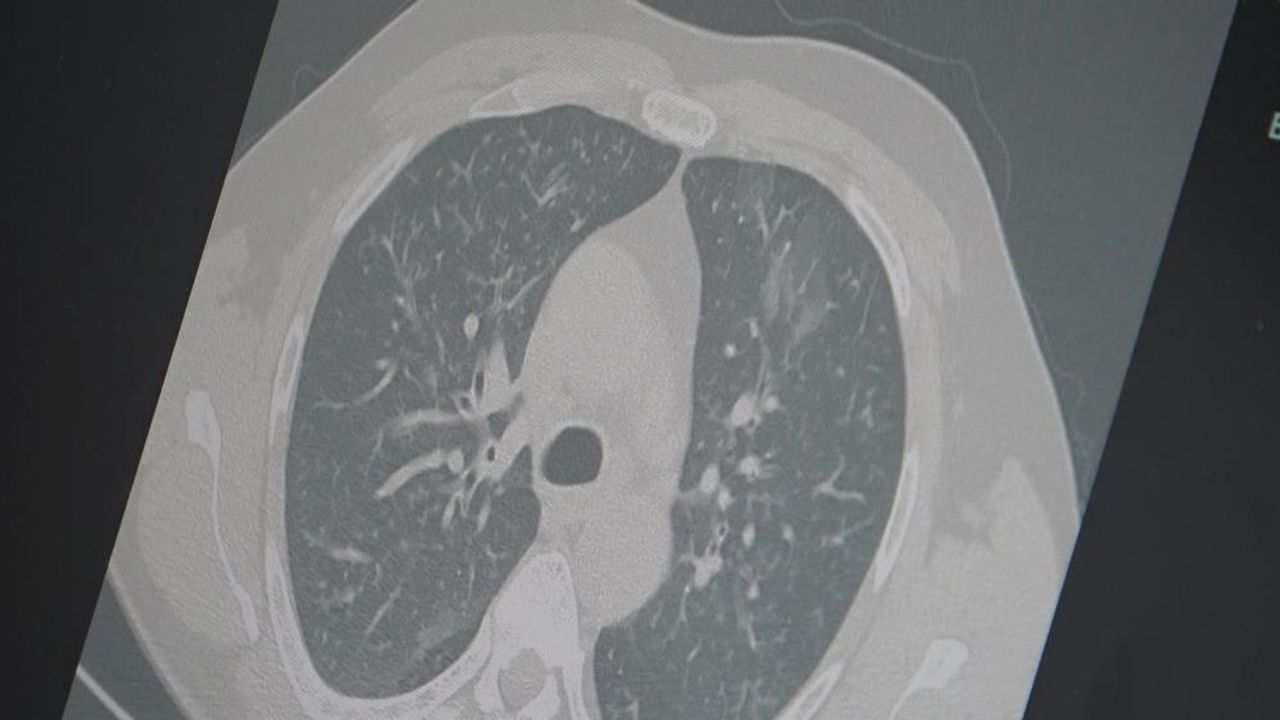

Dr. Özkaya, grip ve kovid 19'un zatürreye dönüşme riski taşıdığını vurgulayarak, "Grip veya kovid sonrası birçok hastamızda hastalık akciğerlere iniyor ve zatürre olarak karşımıza çıkıyor. Hastaneye yatan hasta sayısında da artış gözlemliyoruz" şeklinde konuştu.

"En ufak grip benzeri şikayeti olan vatandaşlarımızın evlerinde dinlenmelerini öneriyoruz. Uzamış öksürük ve nefes darlığı yaşayanların ise mutlaka doktora başvurarak akciğer röntgeni çektirmeleri ve uygun tedaviyi almaları gerekiyor."